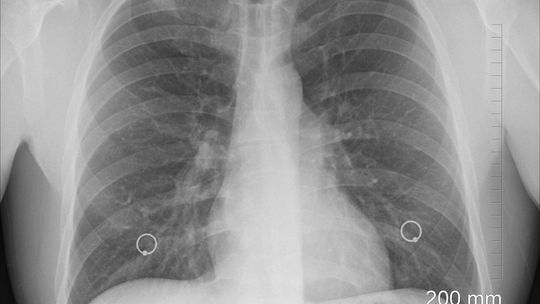

Dr Nauk Medycznych MAREK SZAROCH jest znakomitym i uznanym pulmonmologiem przyjmującym mi. w Centrum Medycznym ESKULAP w Ciechanowie, dlatego został zaproszony przez Radio Rekord 88,7 FM jako ekspert w dziedzinie chorób płuc do cyklu audycji "Zdrowie i Uroda".